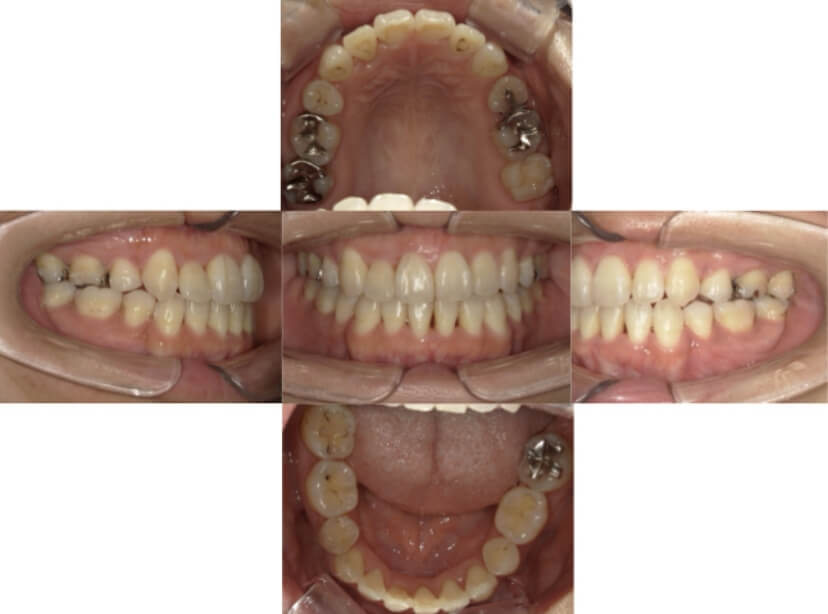

BEFORE

AFTER

症例2

上下顎前突、叢生

抜歯

ブラケット矯正

上下顎前突、叢生(上下出っ歯、上下の前歯のガタガタ)のケースです。

装置はラビアル(上下表側)で、上下顎の小臼歯を4本抜歯を行っています。抜歯したスペースを使って、上下の前歯の後方移動と叢生(ガタガタ)の改善を行っています。

主訴 前歯のガタガタと口元がでているのが気になる。

年齢・性別 30歳 女性

お住まいの地域 東京都大田区

治療方針 抜歯スペースを利用して上前歯の叢生(ガタガタ)と口元突出の改善

抜歯部位 上下顎左右第一小臼歯

使用装置 ラビアル(上下表側)、顎間ゴム

治療期間 1年11か月

治療回数 13回

リテーナー クリアリテーナー